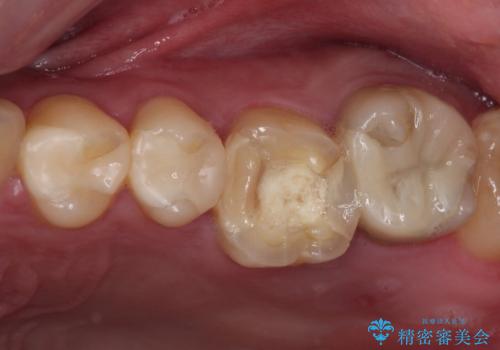

指摘された虫歯 オールセラミッククラウンによる補綴治療